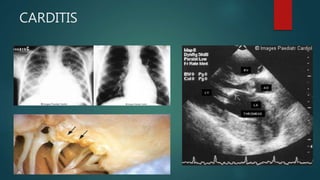

CARDITIS

 It is a pancarditis, but valvular involvement is the rule.

 The commonest involved valve is the mitral, frequently associated with aortic valve involvement.

 On pathological examination, the valves are thickened and display rows of small vegetations

(Aschoff body) along their apposing surfaces.

 The clinical picture includes high pulse rate, congestive heart failure, arrhytmias and pericardial

friction rubs.

 Murmurs:

 Valvulitis – low pitched mid diastolic murmur at apex (Carey Coombs)

 Mitral regurgitation – mid frequency pansystolic murmur

 Aortic regurgitation – high pitched decrescendo diastolic murmur.

 Cardiomegaly on CXR and Echocardiogram.

CARDITIS  It isa pancarditis, but valvular involvement is the rule.  The commonest involved valve is the mitral, frequently associated with aortic valve involvement.  On pathological examination, the valves are thickened and display rows of small vegetations (Aschoff body) along their apposing surfaces.  The clinical picture includes high pulse rate, congestive heart failure, arrhytmias and pericardial friction rubs.  Murmurs:  Valvulitis – low pitched mid diastolic murmur at apex (Carey Coombs)  Mitral regurgitation – mid frequency pansystolic murmur  Aortic regurgitation – high pitched decrescendo diastolic murmur.  Cardiomegaly on CXR and Echocardiogram.